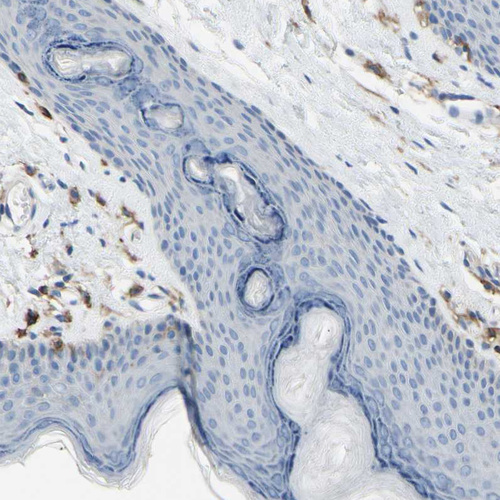

Immunohistochemical staining of human lung shows strong cytoplasmic/membranous positivity in macrophages.